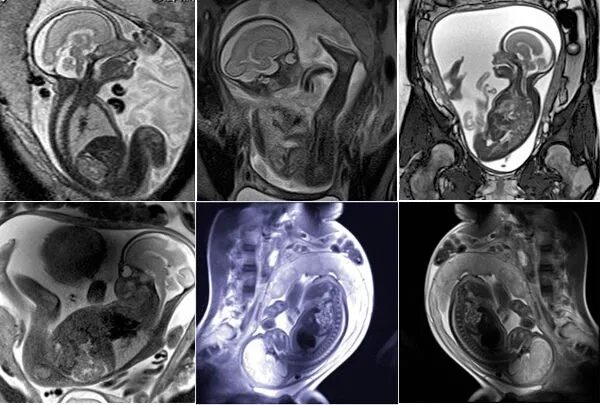

Делала рентген при беременности